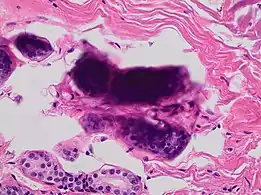

In microscopy

In microscopy, an artifact is an apparent structural detail that is caused by the processing of the specimen and is thus not a legitimate feature of the specimen. In light microscopy, artifacts may be produced by air bubbles trapped under the slide's cover slip.[1]

In electron microscopy, distortions may be produced in the drying out of the specimen. Staining can cause the appearance of solid chemical deposits that may be seen as structures inside the cell. Different techniques including freeze-fracturing and cell fractionation may be used to overcome the problems of artifacts.[1]

A crush artifact is an artificial elongation and distortion seen in histopathology and cytopathology studies, presumably because of iatrogenic compression of tissues. Distortion can be caused by the slightest compression of tissue and can provide difficulties in diagnosis.[2][3] It may cause chromatin to be squeezed out of nuclei.[4] Inflammatory and tumor cells are most susceptible to crush artifacts.[4]